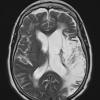

Infarct, Tract Degeneration, illustrative case (2)